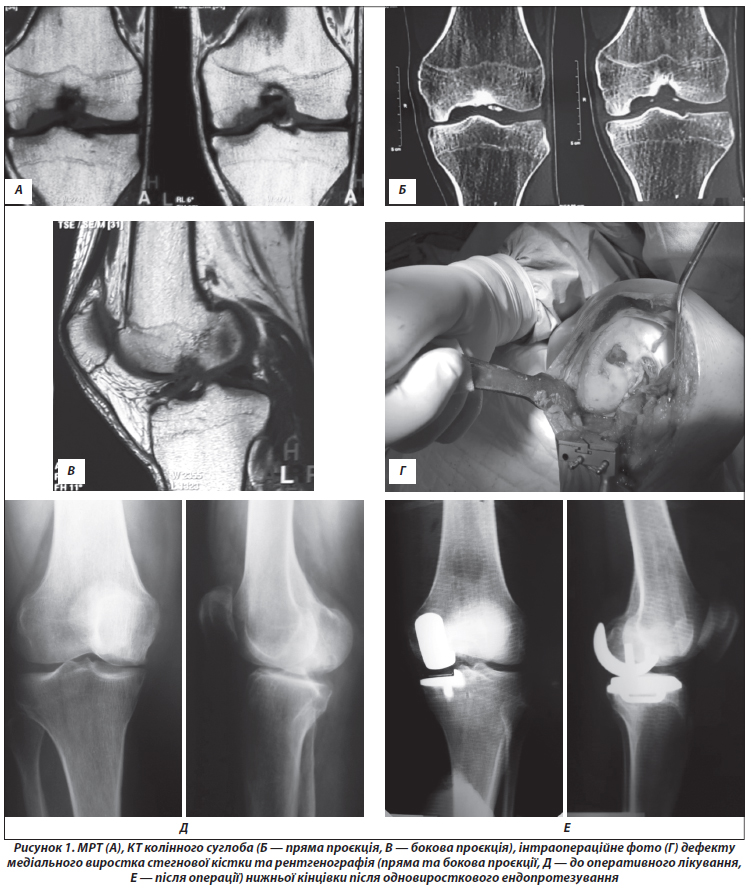

Актуальність. Серед методів хірургічного лікування ранніх стадій медіального гонартрозу все частіше використовується одновиросткове ендопротезування колінного суглоба (ОЕКС). Збільшення кількості ОЕКС медіального відділу підтверджується даними різних національних реєстрів. Мета дослідження: вивчити функціональні результати ОЕКС та проаналізувати ускладнення на різних етапах післяопераційного періоду. Матеріали та методи. Вивчено результати оперативного лікування 29 пацієнтів у період з 2016 по 2021 р. Оцінку функції колінного суглоба та якості життя пацієнтів проводили з використанням шкал-опитувальників Knee Scoring System (KSS), Western Ontario and McMaster Universities Arthritis Index (WOMAC) до операції та через 3, 6, 9, 12, 18 міс. після її виконання. Оцінку функціонального стану пацієнтів за KSS та WOMAC вираховували у відсотках від максимально можливої суми балів за кожною шкалою. Результати. Поліпшення якості життя та функціонального стану зареєстровано в період від 3 до 18 міс., отримано поліпшення показників KSS (79,4 %, р = 0,03), WOMAC (27,1 %, р = 0,02) порівняно зі станом до оперативного втручання (32,3 та 73,6 % відповідно). Відзначена негативна кореляція між індексом маси тіла й функціональним результатом (R = –0,7; р = 0,03). У післяопераційному періоді виявлено ускладнення у 3 пацієнтів, з яких одному хворому виконано ревізійне оперативне втручання, а двом проводили консервативне лікування. Висновки. ОЕКС дозволяє досягти поліпшення якості життя та функціонального стану вже на ранніх термінах (від 3 до 18 місяців) після операції. Удосконалення операційної техніки, аналіз помилок та регулярне виконання хірургом операцій ОЕКС дозволять поліпшити результати та мінімізувати кількість ускладнень. Одновиросткове ендопротезування є операцією вибору для пацієнтів з ізольованим ураженням лише одного з відділів колінного суглоба, яка дозволяє зберегти досить високий рівень фізичної активності.